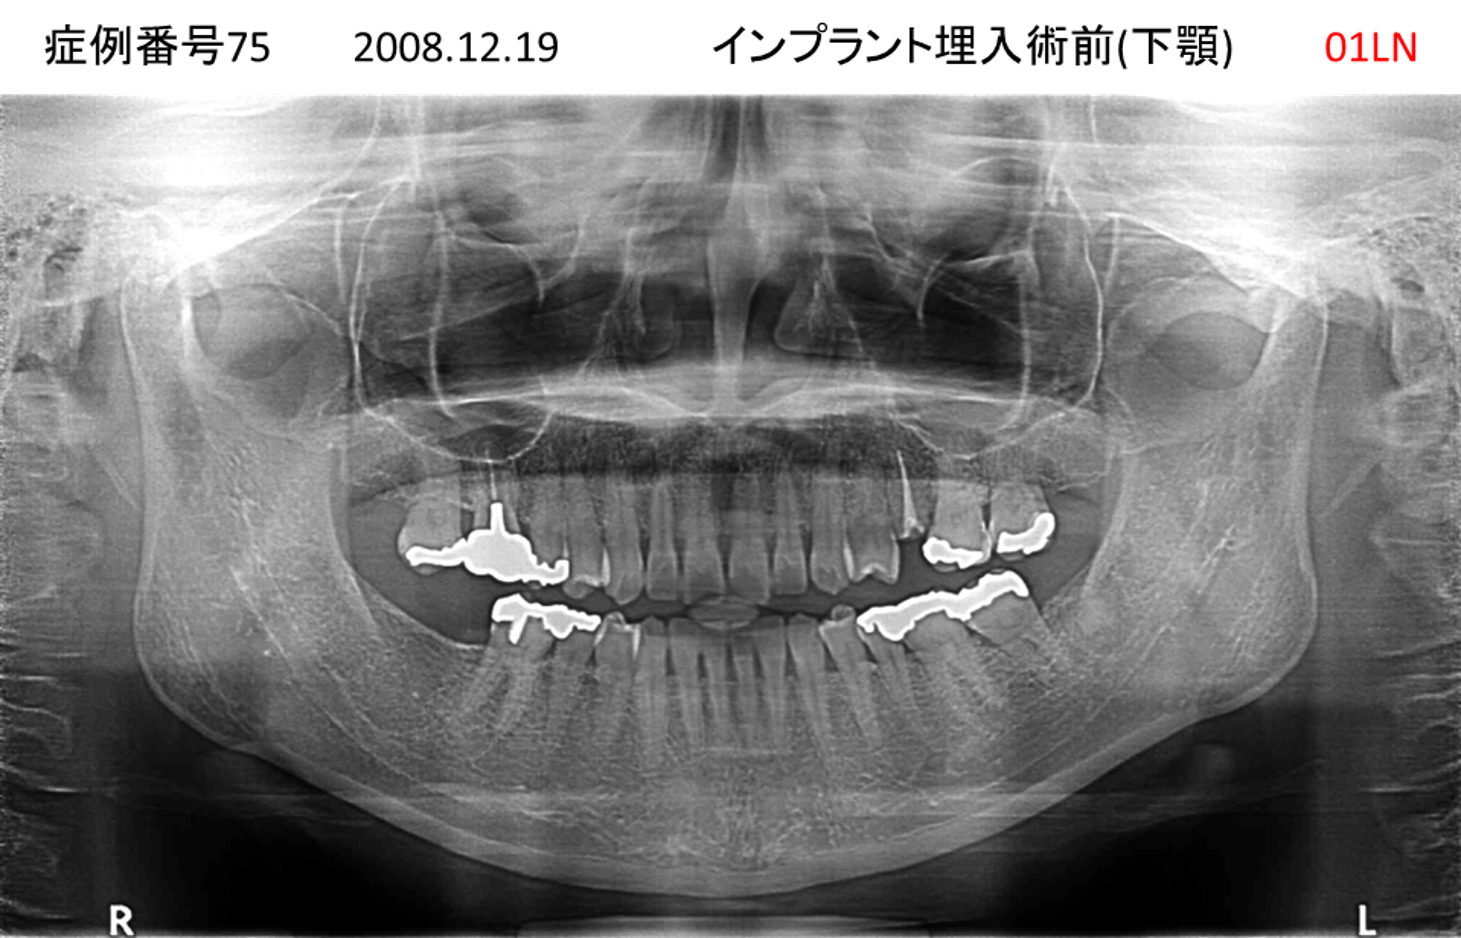

義歯が合わない、噛めない患者様のインプラント症例

| 治療名称 |

インプラントコーヌステレスコープ |

| 治療費用 |

270万円+税 |

| 治療期間 |

4か月 |

| 患者さんの症状(主訴) |

義歯が合わない、噛めない |

| 治療内容 |

インプラント、義歯作製(コーヌステレスコープ) |

| 治療結果 |

しっかり噛めるようになった。見栄えが良くなった。 |

| 治療の注意点(リスク/副作用) |

義歯が壊れた場合、インプラントが壊れた場合は再治療が必要 |